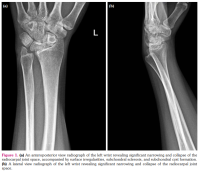

An X-ray of the left wrist (Figures 1a, b) revealed significant narrowing and collapse of the radiocarpal joint space, accompanied by surface irregularities, subchondral sclerosis, and subchondral cyst formation. No posttraumatic bone fractures were detected, and the soft tissues appeared normal. Subsequent imaging with MRI showed a further increase in the pronounced narrowing and collapse of the radiocarpal joint space, along with bone marrow edema in the subchondral region. Osteophytes were detected, along with subchondral cystic changes. Notably, marked synovitis was observed in the radiocarpal and distal radial ulnar joints. Mild radiocarpal and ulnar deformity was present, characterized by increased radial length and an ulnar slant angle, mild distal ulnar subluxation, and hypertrophy of the ulnar styloid process, consistent with the features of Madelung's deformity (Figure 2).